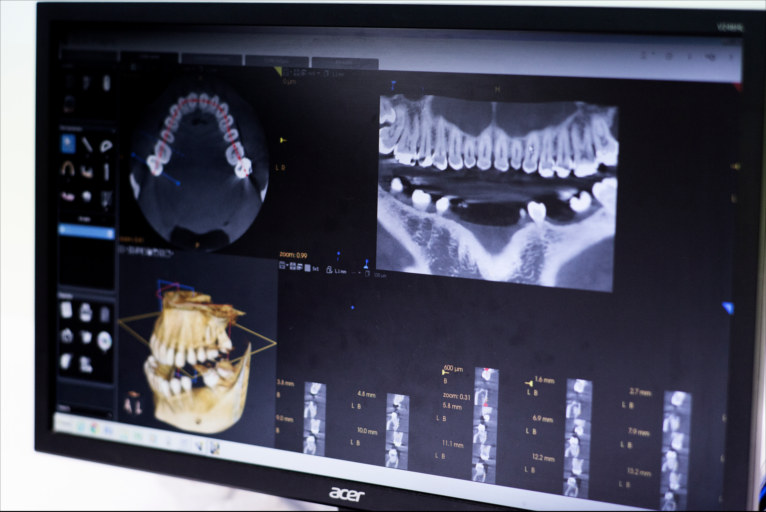

Inplantea

Esperientzia, teknologia eta kalitatea.

- 20 urteko baino gehiagoko esperientzia

Zirugia

- Hezur eta entzien txertaketa

- Periodontala eta periimplantarioa

- Biomaterialak